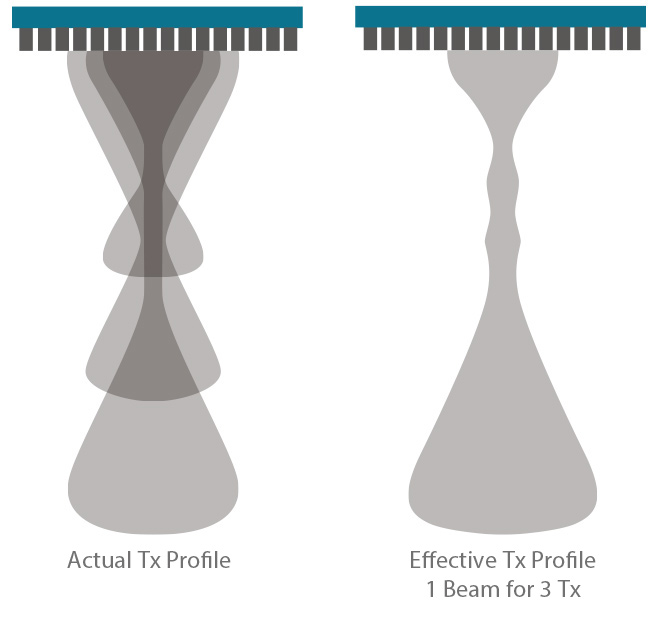

Enfoque de zona

La plataforma ZST+ realizó el enfoque de zona en todo el campo de visión con tecnología de enfoque dinámico de píxeles, asegurando que las imágenes desde la piel superficial hasta la profundidad Los órganos de cualquier animal están en el estado de enfoque en tiempo real.

Enfoque múltiple basado

En la formación de haces tradicional

Enfoque tradicional

Enfoque dinámico de píxeles basado

En ZONE Sonography™

Tecnología ZONE Sonography™+